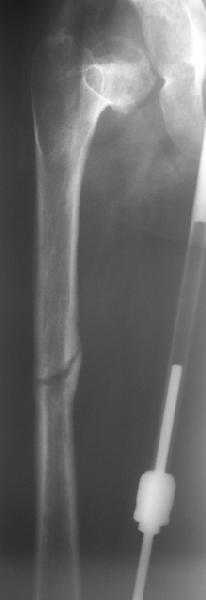

15.08.2007 в ЦРБ сделан открытый остеосинтез правого бедра интрамедуллярным стержнем, после чего была наложена гипсовая кокситная повязка и пациентка лечилась амбулаторно в течение 1,5 месяцев. На контрольном Rn исследовании в марте 2008 диагностирован подвздошный вывих правого бедра.

Поступила к нам в отделение. В отделении первым этапом был наложен аппарат внешней фиксации для низведения бедра. 30.09.08 интрамедуллярный стержень удален. Вторым этапом планируется эндопротезирование. В настоящее время у больной имеется контрактура коленного сустава, с амплитудой движений в пределах 30 градусов., и выраженный остеопороз вертлужной впадины и проксимального отдела бедра. Больныя пердвигается самостоятельно с опорой на здоровую ногу и костыли.

Какие проблемы при эндопротезиовании в этих условиях ожидать, и как с ними бороться? Еще и диафиз сросся не очень крепко, опасаемся, как бы не сломать. Очень выражен местный остеопороз, может быть, сделать все-таки цементный протез? Хотя 18 лет всего. Спасибо.